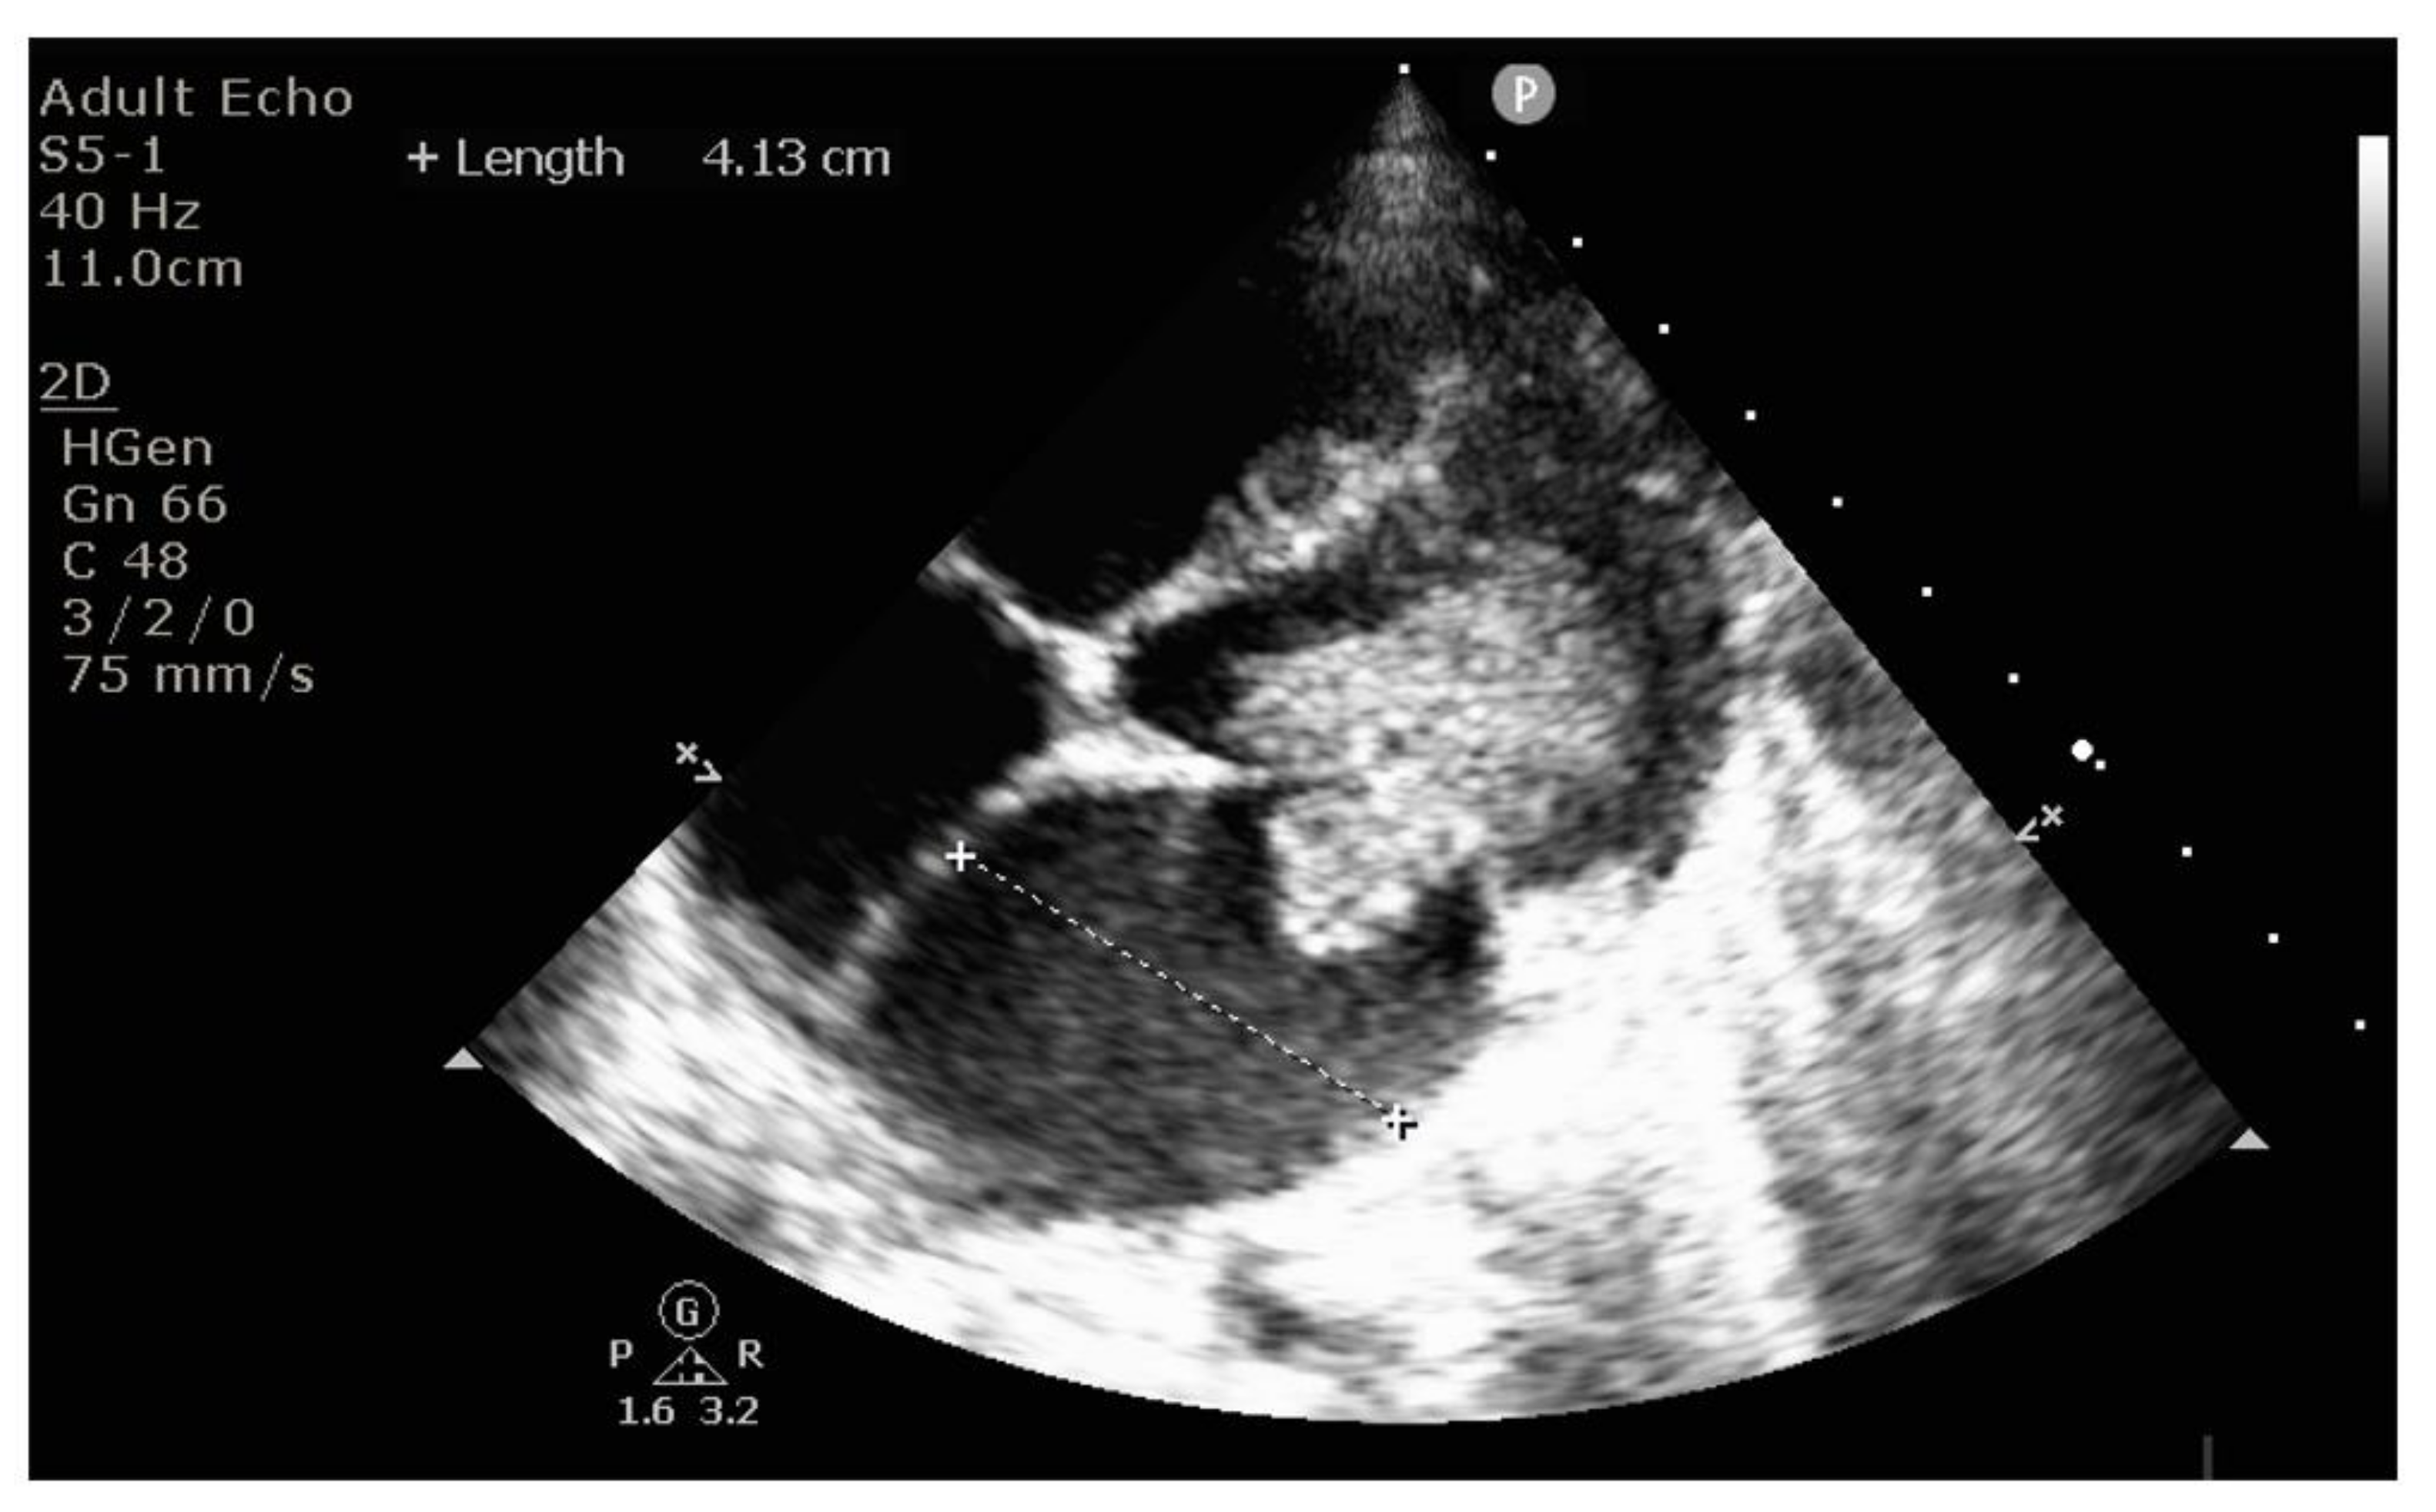

2. Case Report